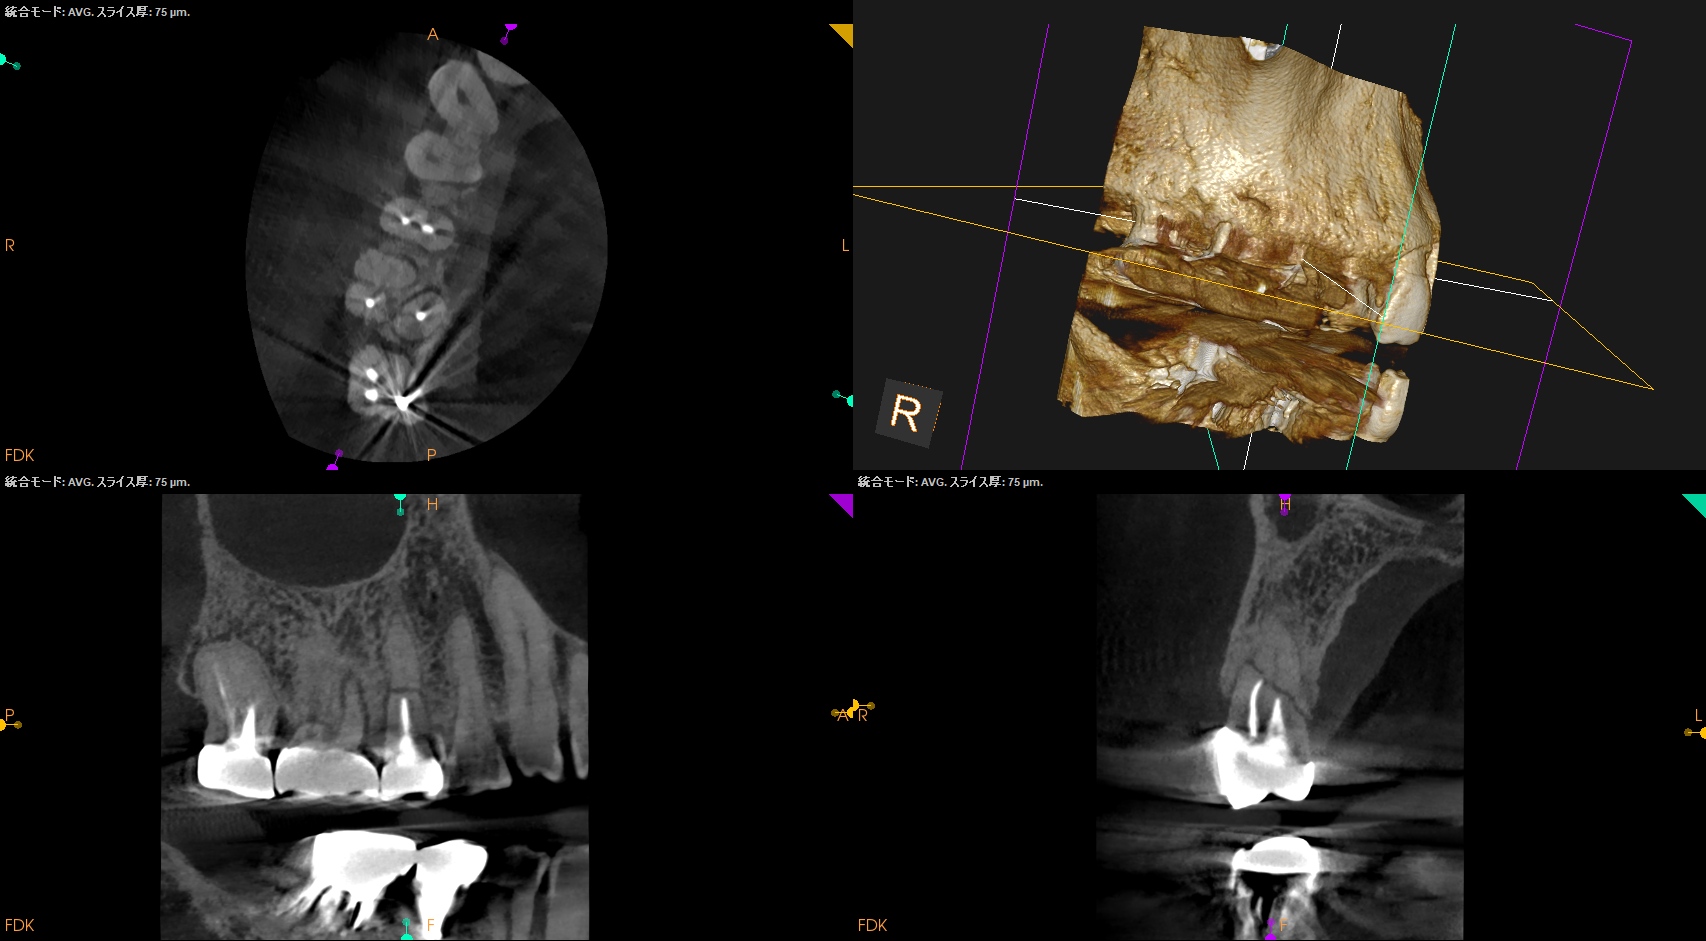

CBCT(2024.10.28)

#4

歯根の中央で水平に破断している。

ここで重要なことは破折片の口蓋側寄りの歯根には病変がないということだ。

ということは…

そこは根管治療が不要である。

治療のゴールとしては、

このような形状に落ち着くのがベストであると言えるだろう。

もしその上部の根尖部に何かが起これば?

それはそこだけ抜歯であろう。